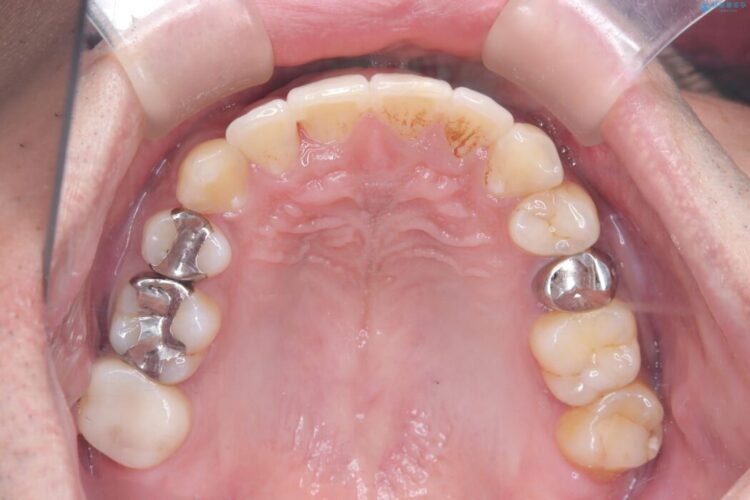

噛み合わせのズレが右側で大きかった(2級)ため、右側上下2本の歯を抜歯し、ワイヤー矯正で噛み合わせを左右対称の理想的な位置に改善しました。

気になっていた八重歯や凸凹が改善され、大変ご満足いただけました。